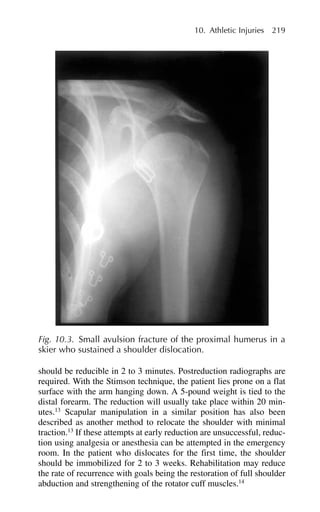

10 Athletic Injuries Michael L.Tuggy and Cora Collette Breuner Family physicians routinely treat many athletic injuries in their clini- cal practice. The benefits of long-term exercise in the prevention of common illnesses such as cardiovascular disease, osteoporosis, and falls in the elderly are well established. With the increased interest in fitness in the general population, the number of people resuming more active exercise as they age is increasing. Injuries sustained in child- hood or adolescence may have long-term effects that can hamper later attempts at physical activity.1 For all ages of patients, proper training and prevention can lead to lifelong participation in athletic activities. Most sports injuries are related to overuse injuries and often are not brought to the attention of the family physician until the symptoms are advanced. Traumatic injuries are more readily diagnosed, but may have more serious long-term sequelae for the life of the athlete. Sport selection has a great impact on risk of injury. The adolescent athlete is probably at highest risk for injury due to sport selection, presence of immature growth cartilage at the growth plates and joint surfaces, and lack of experience.2 High-risk sports selected by young adults also have higher degrees of risk, which can be modified to lessen injury rates by training and education. Table 10.1 lists common sports activities and their relative injury rates. Mechanisms of Injury Direct trauma is a common mechanism that leads to injury. Deceleration injuries are the most common form of serious injury,

• 220.

resulting in significantblunt trauma or joint injury. The athlete’s momentum, enhanced by self-generated speed, gravity, and equip- ment, is translated into energy when impact occurs. This energy is then absorbed by the body in the form of blunt trauma, torsion of joints, or transfer of stress within the skeleton. Collision sports, such as football or rugby, and high-velocity sports, such as alpine skiing, have much higher rates of significant muscu- loskeletal injury due to the combination of speed and mass effect on impact. Factors that affect the extent of injury include tensile strength of the ligaments and tendons of affected joints, bony strength, flexi- bility, and ability of the athlete to reduce the impact. This is where appropriate conditioning for a sport reduces injury risk. Not only are endurance and strength training important, but also practicing falls or recovery from falls can help the athlete diffuse the energy of the fall or impact. Athletes should be encouraged to use the appropriate safety equipment and to train comprehensively for their sport. Overuse injuries comprise the most common form of sports injuries seen by the family physician. These injuries are induced by repetitive motion leading to microscopic disruption of a bone–tendon or bone– synovium interface. This microtrauma initiates an inflammatory 206 Michael L. Tuggy and Cora Collette Breuner Table 10.1. Common Sports Injuries and Injury Rates Injury rate Sports (per 1000 activity Common injuries exposures) Running Tibial periostitis, stress fracture 14 Metatarsal stress fractures Football ACL/MCL tears Shoulder dislocation/ 13 separation Ankle sprain Wrestling Shoulder dislocation MCL, LCL tears 12 Gymnastics Spondylolysis/spondylolisthesis 10 Ankle sprains Alpine/telemark ACL/MCL tears 9 skiing Skier’s thumb Shoulder dislocation Basketball Ankle sprains 4 Shoulder dislocation/separation Baseball Lateral epicondylitis Rotator cuff tear 4 Cross-country Ankle sprains Lateral epicondylitis 3 skiing ACL ⫽ anterior cruciate ligament; LCL ⫽ lateral collateral ligament; MCL ⫽ medial collateral ligament.

• 221.

response. If theinflammatory response is not modulated by a rest phase or is excessive due to mechanical factors, then degradation of the tendon or bone may occur. Predisposing factors that lead to overuse injuries include poor flexibility, imbalance of strength of opposing muscle groups, mechanical deformity (e.g., pes planus), inadequate rest between exercise periods, and faulty equipment.3 Adolescent ath- letes are especially vulnerable to such injuries, especially in areas where growth cartilage is present in the epiphyseal or apophyseal attachments of major muscle groups. Elderly athletes also are at higher risk because of preexisting degenerative joint disease (DJD) and poor flexibility. Overuse injuries can be classified in four stages. Stage 1 injuries are symptomatic only during vigorous exercise and stage 2 during moder- ate exercise. Stage 3 injuries are symptomatic during minimal exercise, and the symptoms usually last up to 24 hours after exercise has ceased. Stage 4 injuries are painful at rest with no exercise to exacerbate the symptoms. Most overuse injuries are seen at later stages by physicians (stage 3 or 4) and require significant alteration in training schedules to allow healing of the injury. Progressive inflammation from overuse can eventually lead to tendon disruption, periostitis (stress reaction), true stress fractures, or cartilaginous degeneration. Early periostitis may only appear as a “fluffiness” of the cortical margin with compensatory cortical thickening underlying it (Fig. 10.1). In more advanced cases, the margin is clearly blurred and the cortex significantly thickened. If symptoms suggest a significant stress reaction but x-rays are negative, then a bone scan is indicated. True stress fractures can be visualized on plain film while stress reactions (periostitis) are best seen on bone scan. Because stress fractures are inflammatory in nature, the compli- cation rates due to delayed or nonunion are higher than those with trau- matic fractures.4 The results of improper treatment of these injuries can be severe, resulting in permanent degenerative changes or deformity. The primary care provider plays an important role not only in diag- nosing the injury early (and thus shortening the rehabilitation period) but also in stressing prevention with proper training guidance and timely intervention. Traumatic Injuries Physicians providing coverage for athletic events must recognize high-risk situations for serious injuries and evaluate the safety of the sports environment. Asking the following questions when first evaluating a patient with a traumatic injury helps suggest the correct 10. Athletic Injuries 207